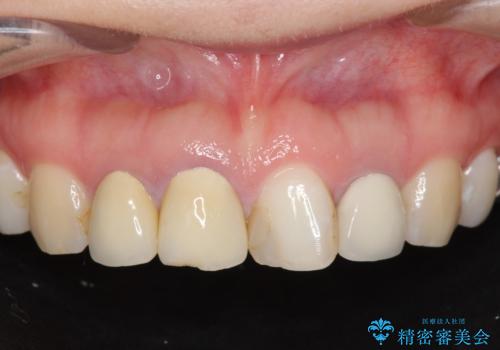

前歯の見た目を改善したい

- 前歯を天然の歯のようにきれいにやりかえたいと希望され来院されました。

審美的なジルコニアクラウンを装着し、審美性が回復されたと満足いただくことができました。